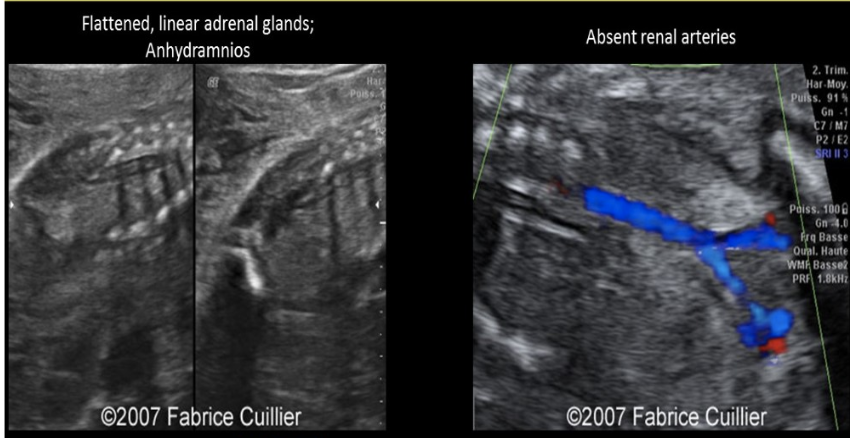

what congenital anomaly is shown

a) renal agenesis

b) duodenal atresia

c) anal atresia

d) posterior urethral valves